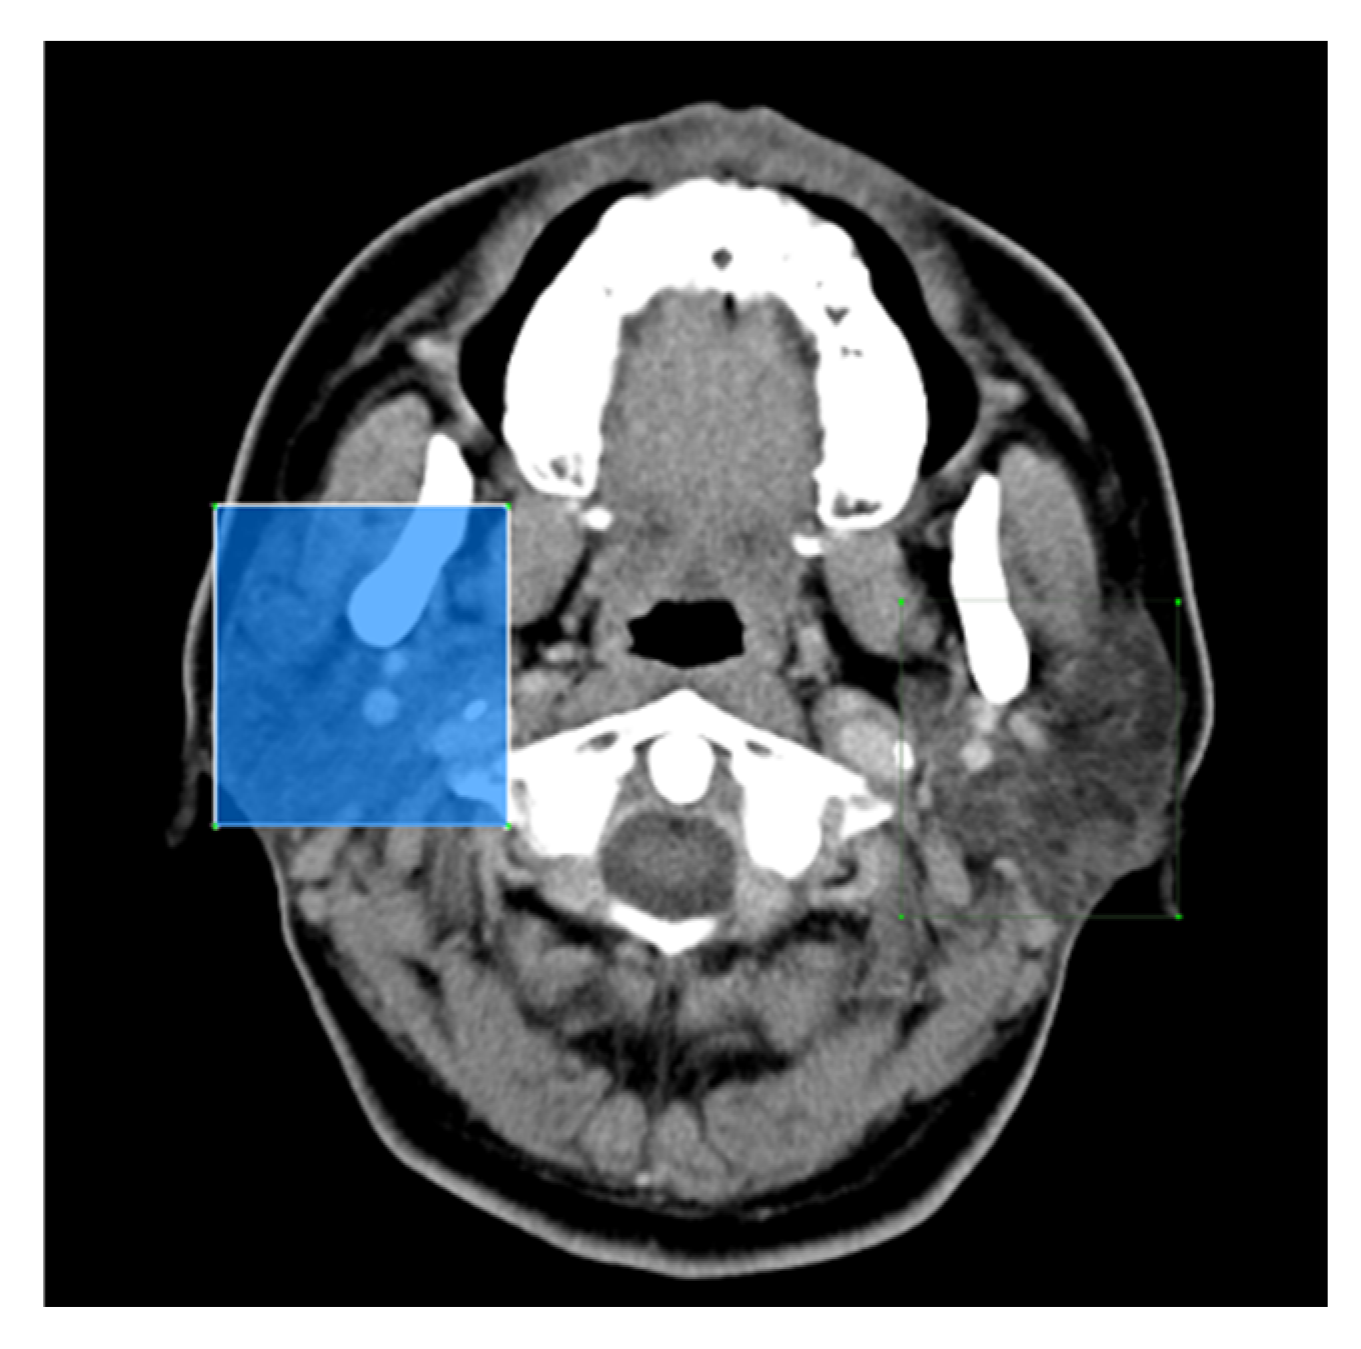

In this study, head and neck CT images were sourced from the ENT CLINIC of National Cheng Kung University Hospital. All scans were performed using the SOMATOM Definition AS (Siemens, Germany) with the following parameters: tube current set to CARE Dose 4D quality reference at 180 mAs, tube voltage at 120 kVp, slice thickness and interval of 5 mm, and a display field of view of 22 cm. The scanning range extended from the skull’s base to the thoracic cavity’s entrance. Enhanced images were acquired following the intravenous injection of 60–100 mL of contrast agent (350 mg/mL; Xenetix®, Guerbet, Villepinte, Paris, France) at a rate of 2.0 mL/s, followed by 20 mL of normal saline. The captured images had a 512 × 512 resolution pixels with a pixel width of 0.41 mm. The experimental dataset comprised 4,183 CT images, of which 3,436 were labeled, while 747 remained unlabeled due to the absence of identifiable parotid glands. The dataset included 232 patients, consisting of 64 diagnosed with malignant tumors and 168 with benign tumors. The gender distribution was predominantly male, with a male-to-female ratio of 6:4; the average patient age was 66 years. An original CT image is presented in Figure 2a.

For this study, the LabelMe software [11] was used to assist physicians in annotating the locations of parotid glands and tumors, resulting in bounding boxes for each identified structure. The annotations were categorized into eight distinct classes: left parotid gland, right parotid gland, left malignant tumor, right malignant tumor, left mixed tumor (pleomorphic adenoma), right mixed tumor (pleomorphic adenoma), left Warthin tumor, and right Warthin tumor, as illustrated in Figure 2b. The diagnostic process for classifying tumor types considered factors such as lesion distribution, shape, density, and margins. Clinical observations have noted that pleomorphic adenomas (mixed tumors) carry a potential risk for malignant transformation, whereas Warthin tumors are associated with an extremely low likelihood of malignancy.

Figure 2. (a). Original image. (b). Labeled CT image with annotated regions.